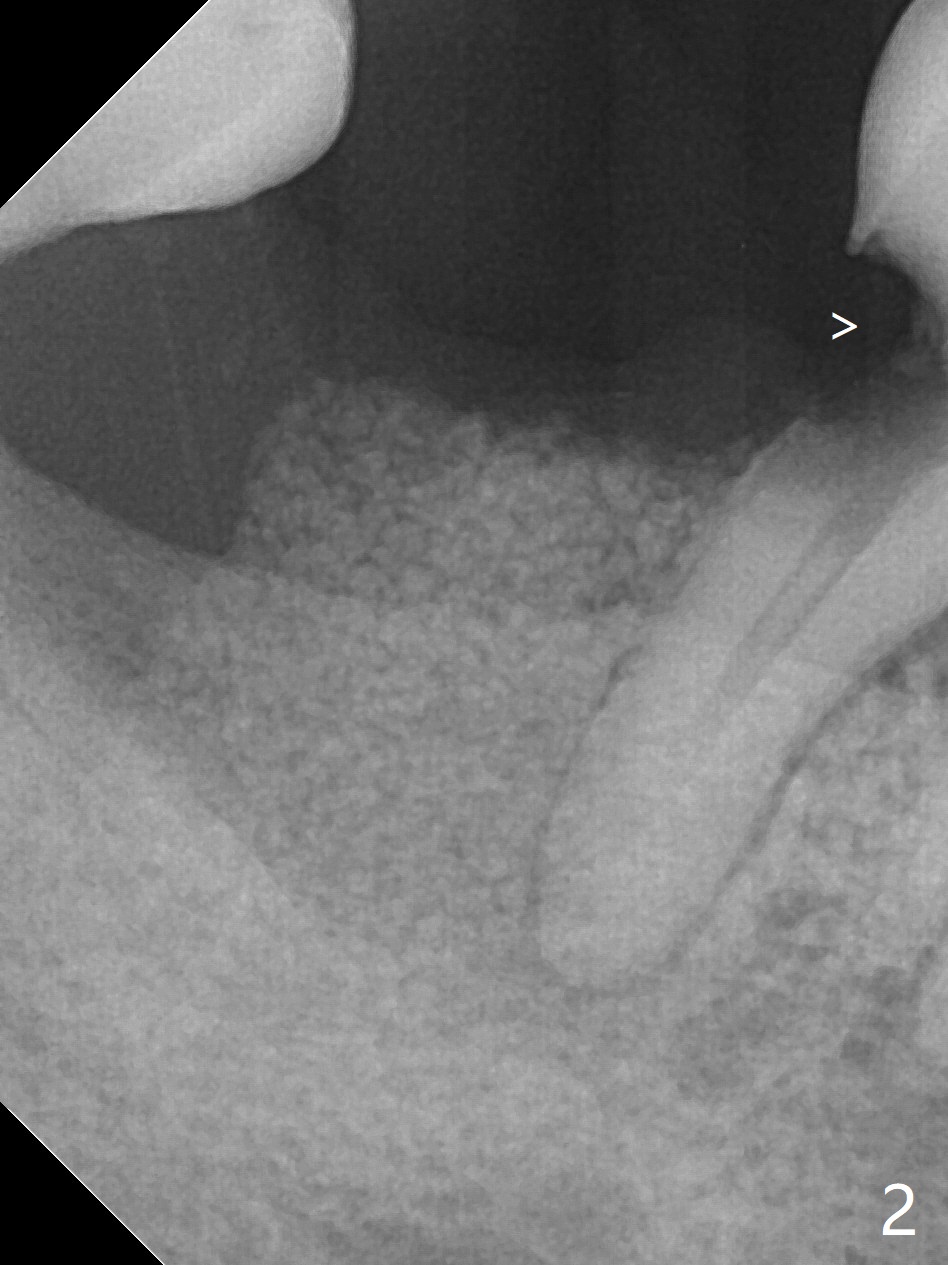

Socket is Larger than Residual Root

A 55-year-old woman has not visited dentists for the last 8 years. She requested extraction of the residual root of #31, although she is sensitive to cold in the area (caries in DO of #30, Fig.1: *). Bone graft was not prepared until the root was taken out. The socket was too big to heal by itself for implant. Bleeding is controlled by insertion of gauze with 1:100,000 Epinephrine. With consent, cortical bone was placed after mixing with blood (Fig.2) and covered with 8x8 mm BioXclude. Acrylic dressing is applied with intention to engagement into the DO of #30 for retention (Fig.2 >). Return to Protect Graft 尖牙即种 Xin Wei, DDS, PhD, MS 1st edition 05/24/2021, last revision 05/31/2021